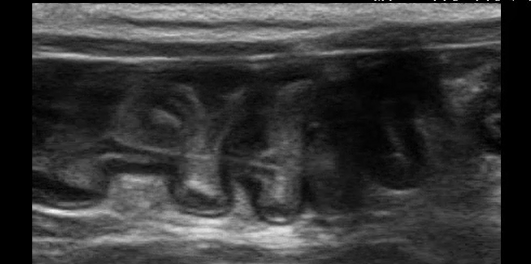

ひもを丸呑み!?〜長いひもが引き起こす、ちょっと怖い誤食の話〜

⚠️ ご注意くださいこの投稿には、手術中の写真や臓器・血液を含む画像が掲載されています。医療的な内容にご関心のある方向けの投稿となっておりますので、出血や臓器の画像が苦手な方は、閲覧をお控えください。 「ひもや糸で遊ぶの […]